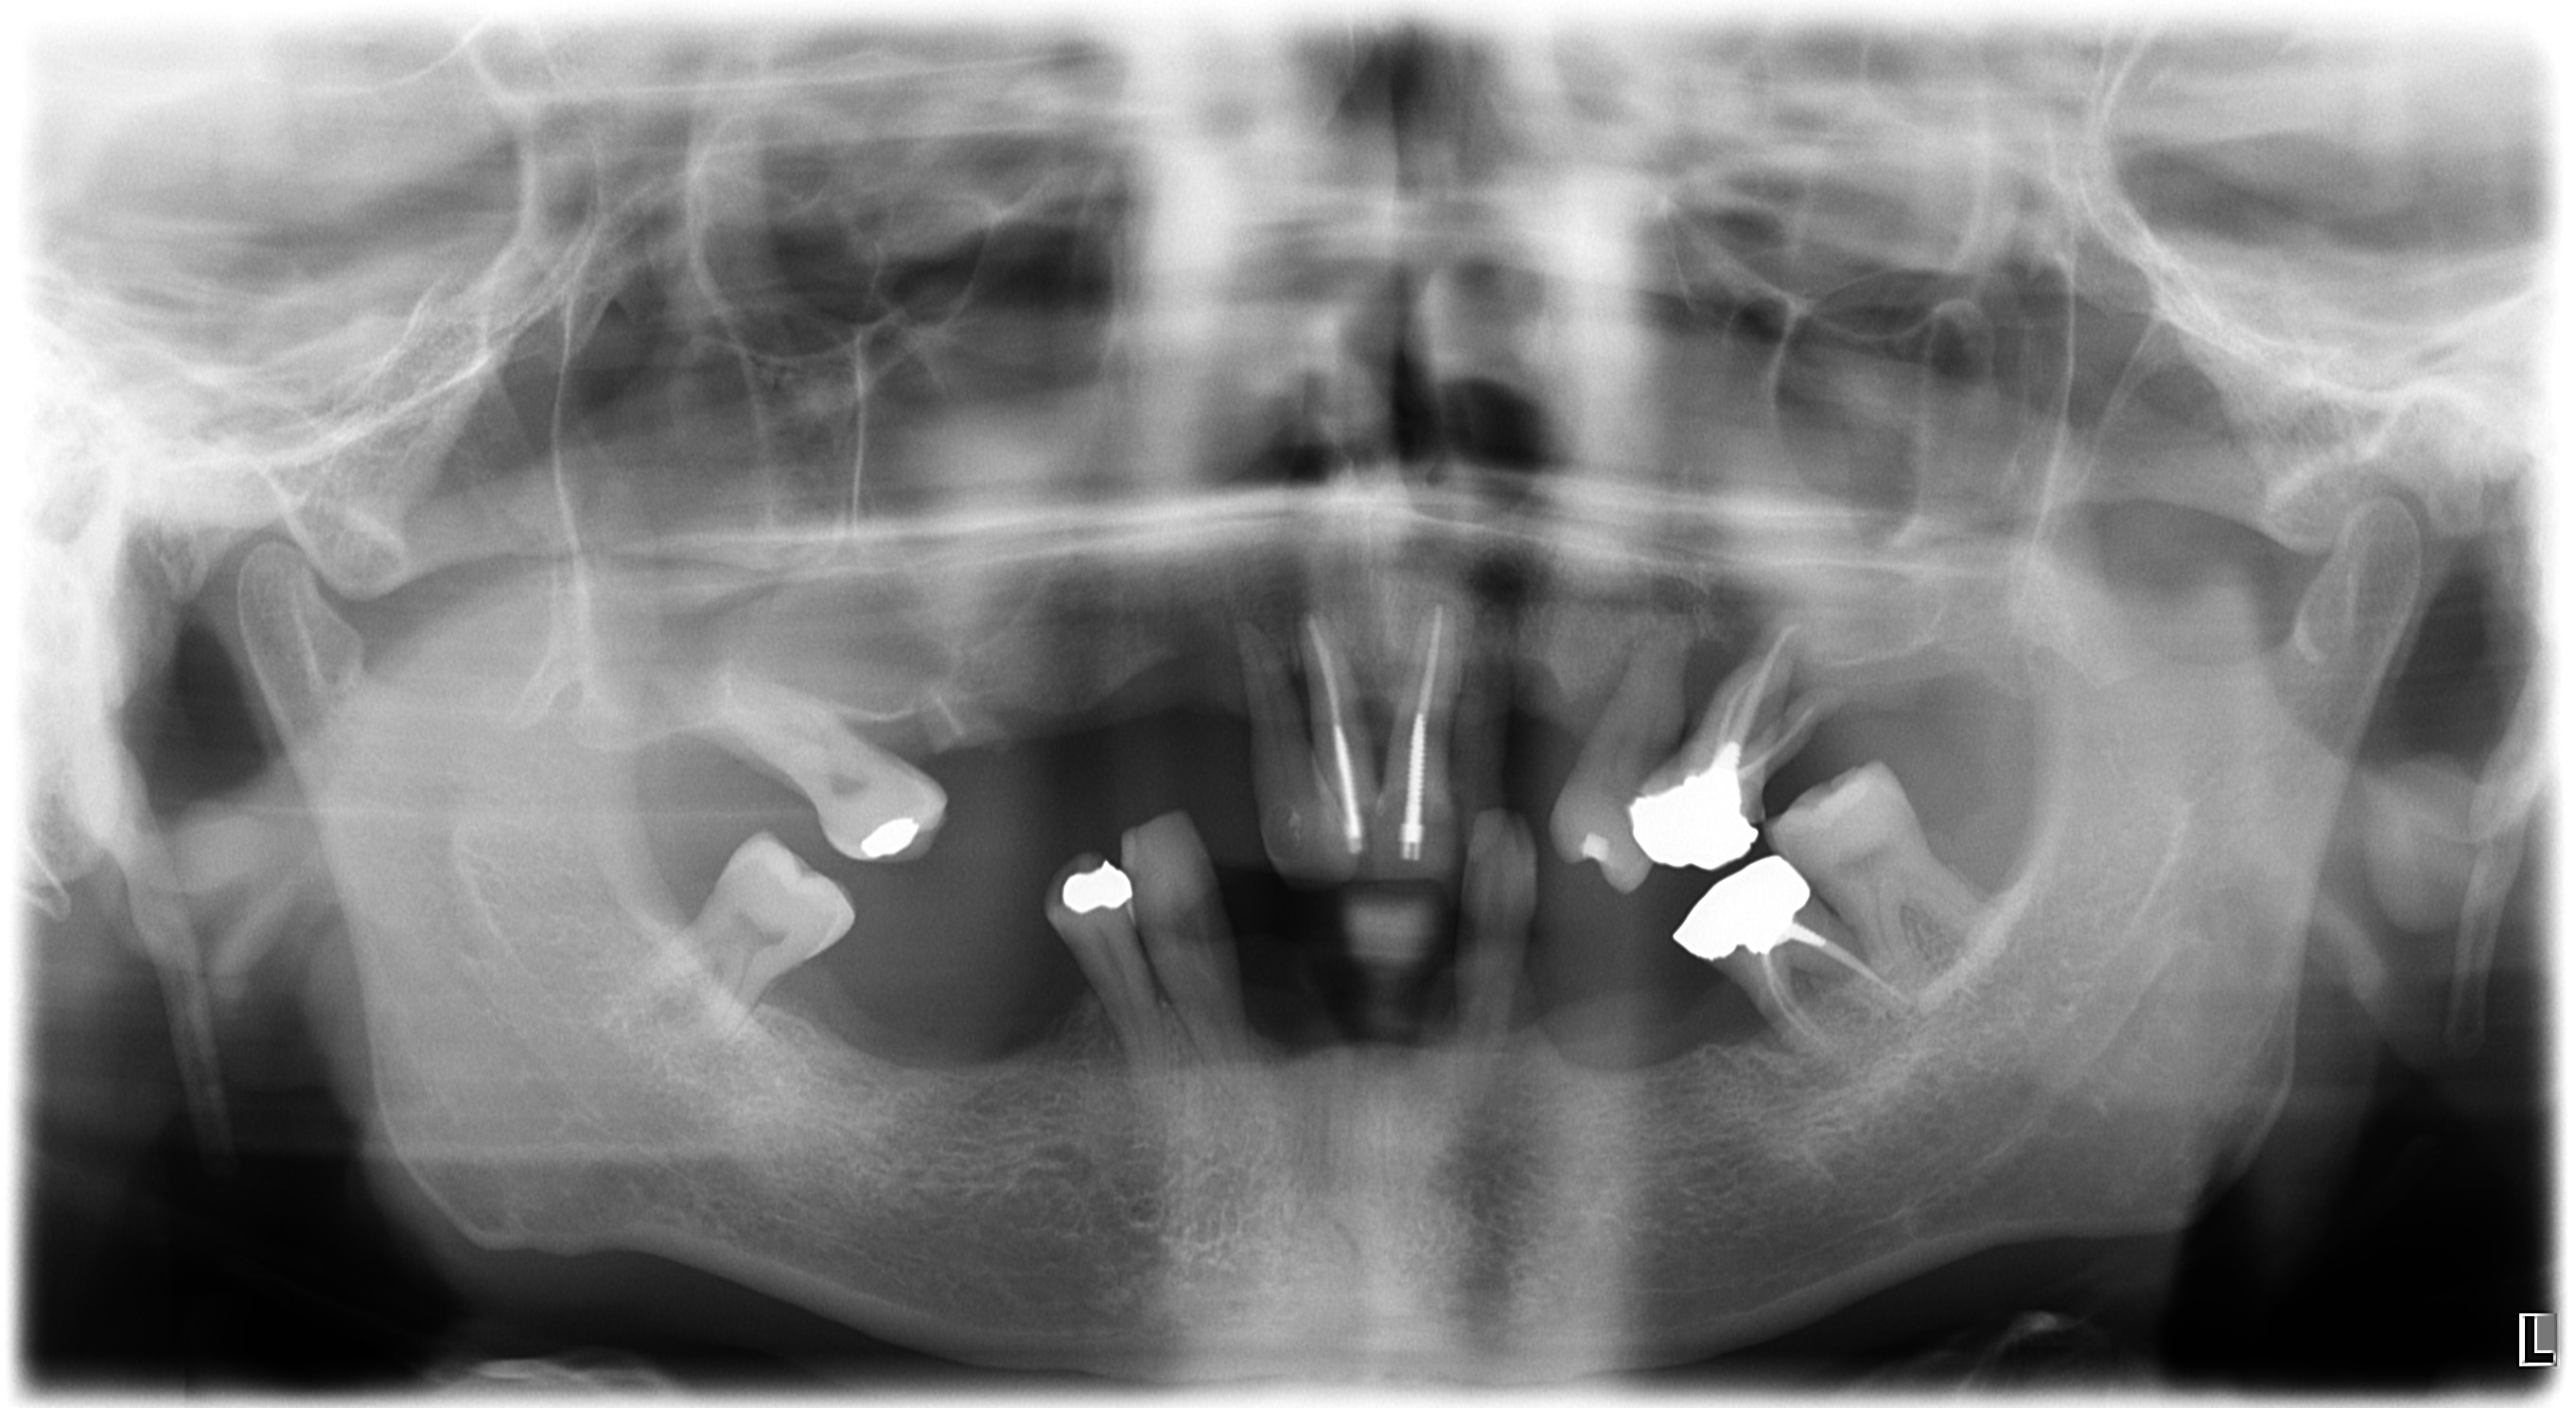

salve volevo un consiglio, mi sono stati proposti soluzioni un intervento per fare 2 impianti zigomatici ma non avendo la masticazione corretta mi sono state proposte 2 protesi mobili da portare x 2 mesi per rimettere a posto la masticazione mascellare e poi procedere a fare gli impianti zigomatici

la seconda proposta sono 4 impianti zigomatici e per correggere la masticazione mascellare con ribasamento della protesi provvisoria grazie a chi mi dara consigli